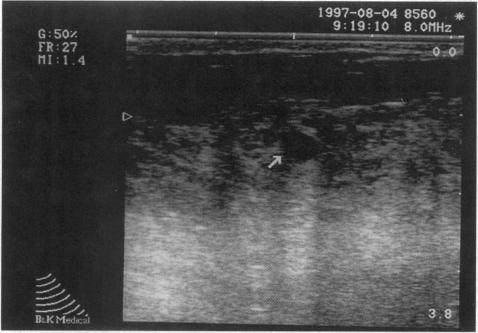

General surgeons perform US examinations of the thyroid gland, breast, gastrointestinal tract, peritoneal cavity (laparoscopy), and vascular system. Essentials of these examinations are discussed and a plan for educating surgical residents in US is outlined.

Focused assessment for the sonographic examination of the trauma patient, or FAST, is replacing central venous pressure measurements to detect hemopericardium and diagnostic peritoneal lavage to detect hemoperitoneum. Bedside US can be used to detect a pleural effusion so well in critically ill patients that lateral decubitus x-rays are rarely needed. US-directed biopsy of breast lesions is a common office procedure. Laparoscopic US allows tumor staging without formal celiotomy, and many hepatic and pancreatic surgical procedures include US as an adjunct. Endoscopic and endorectal US have added a new dimension to the assessment of many gastrointestinal lesions. Color flow duplex imaging and endoluminal US have significantly expanded the diagnostic and therapeutic aspects of vascular imaging. The training program developed at Emory University and Grady Memorial Hospital is offered as a model for educating surgical residents in US techniques.